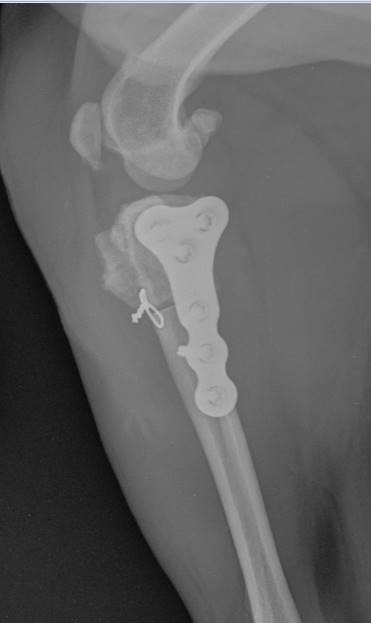

Tibial plateau levelling osteotomies have become popular techniques for the treatment of canine cranial cruciate ligament disease. Whilst it is more invasive than some of the other techniques and involves an osteotomy, there is some evidence that it may produce better results than other surgeries long term. We strongly recommend attending a practical course before attempting these techniques.

UK TPLO Photo